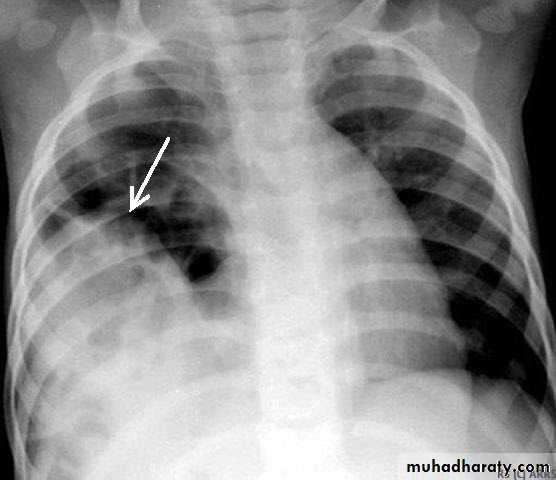

PneumothoraxX-ray pneumothorax

X-ray pneumothorax

Pneumothorax

A: before treatmentB: after treatment